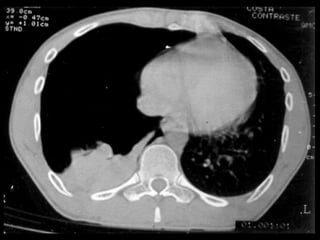

• Diagnóstico

– Radiografia de tórax

– TC de tórax

• Diagnóstico – Anamnese –Exame físico – Radiografia de tórax • Inspiração profunda (A) • Expiração profunda – TC de tórax